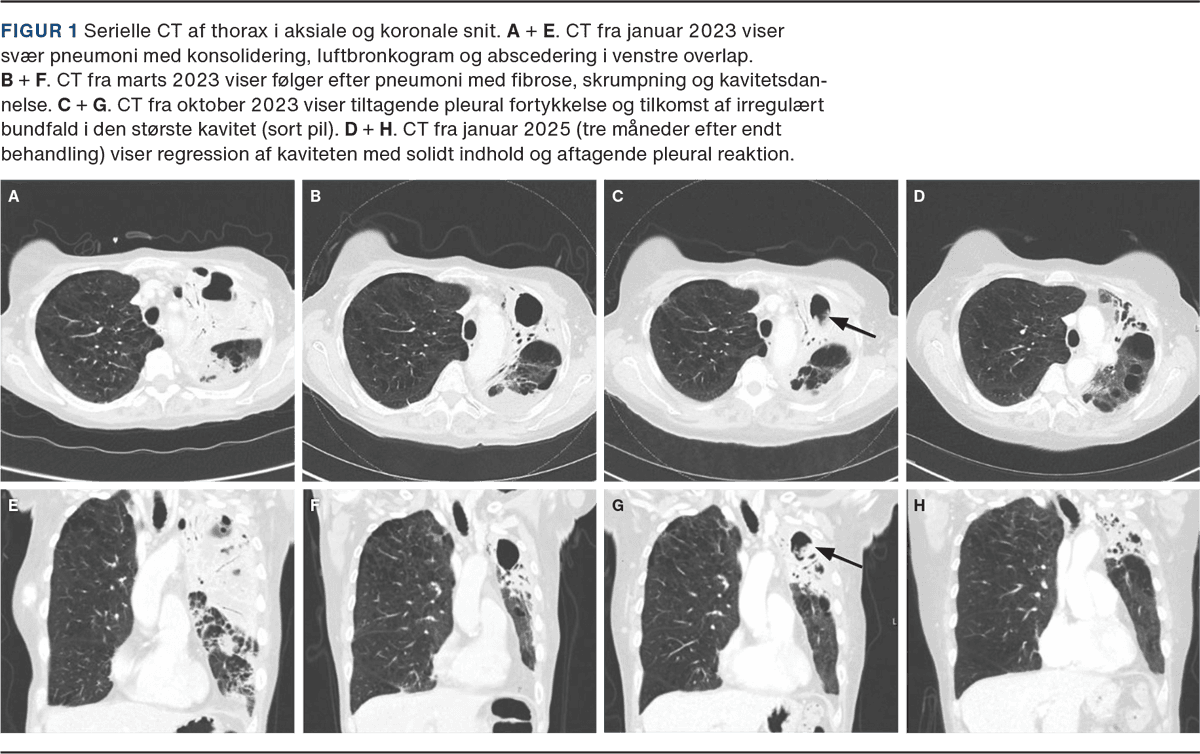

En 68-årig kvinde, diagnosticeret med KOL (GOLD 3E, FEV1 41 %), behandlet med inhaleret langtidsvirkende antikolinergikum (LAMA), samt centrilobulært emfysem af moderat grad, blev i januar 2023 indlagt med svær pneumoni med abscedering i venstre lunge. Under indlæggelsen blev der udført CT af thorax (Figur 1 A + E) samt undersøgelser af ekspektorat, bronkoalveolær lavage (BAL) og blod for bakterier, mykobakterier, vira og svampe. BAL udkom med sparsom vækst af Pseudomonas aeruginosa. Patienten blev behandlet med antibiotika i samlet 32 dage. På klinisk mistanke om et organiserende element tillagde man højdosis prednisolon (50 mg prednisolon dagligt nedtrappet over to måneder, akkumuleret dosis 1.073 mg) med god effekt. En opfølgende CT i marts 2023 viste fibrosering, skrumpning og kavitetsdannelse i venstre overlap (Figur 1 B + F). I april 2023 modtog patienten på mistanke om opblussen en ny prednisolonkur (12,5 mg prednisolon dagligt nedtrappet over tre uger, akkumuleret dosis 273 mg) med godt klinisk respons, og i august 2023 blev patienten igen behandlet med antibiotika og prednisolon (37,5 mg prednisolon dagligt i fem dage, akkumuleret dosis 188 mg) for eksacerbation i KOL og pneumoni. Senere i august 2023 ved ambulant opfølgning beskrev patienten en generel forværring af sin vanlige dyspnø, og der blev derfor tillagt inhalationssteroid/langtidsvirkende beta-2-agonist (ICS/LABA) som inhaleret behandling for KOL.

I oktober 2023 blev patienten indlagt med feber, træthed, dyspnø og hoste. CT af thorax viste tiltagende pleural fortykkelse, konsolidering omkring kaviteterne i venstre overlap samt irregulært bundfald i en af kaviteterne (Figur 1 C + G). Der blev udført bronkoskopi med BAL og transbronkial biopsi samt serologiske undersøgelser. BAL udkom med positiv Aspergillus galactomannan-antigen (AGM) med indeks 4,33 (reference: positiv i BAL ved indeks ≥ 3,0), og Aspergillus fumigatus IgG var forhøjet på 528 mg/l (reference: < 40 mg/l). AGM i blod var negativ. Ti vævsprøver fra venstre overlap blev sendt til histologisk undersøgelse inkl. specialfarvning for svampe. Der var ikke granulomer, nekrose eller tegn på malignitet i biopsimaterialet, og der blev ikke påvist Aspergillus-species eller svampehyfer i biopsimaterialet eller BAL. PCR for Aspergillus blev ikke udført på BAL eller biopsimateriale.

Billedet tolkedes som værende foreneligt med kronisk kaviterende pulmonal aspergillose (CCPA). Patienten blev behandlet med itraconazol, voriconazol, posaconazol og isavuconazol i nævnte rækkefølge. Skift mellem azolerne skyldtes bivirkninger. Interaktionskontrol samt therapeutic drug monitoring (TDM) blev iværksat for alle regimer, og ICS/LABA blev seponeret. Patienten fik samlet et års behandling. Hun responderede godt med regression af kaviteterne på CT (Figur 1 D + H), normalisering af Aspergillus fumigatus IgG samt aftagende symptomer.